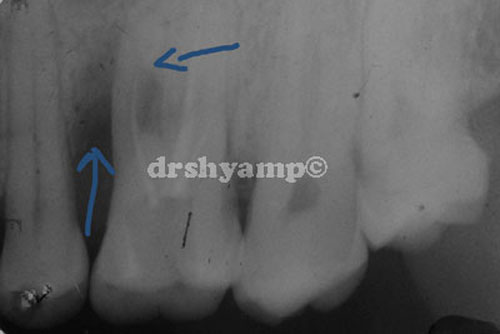

Bone grafting